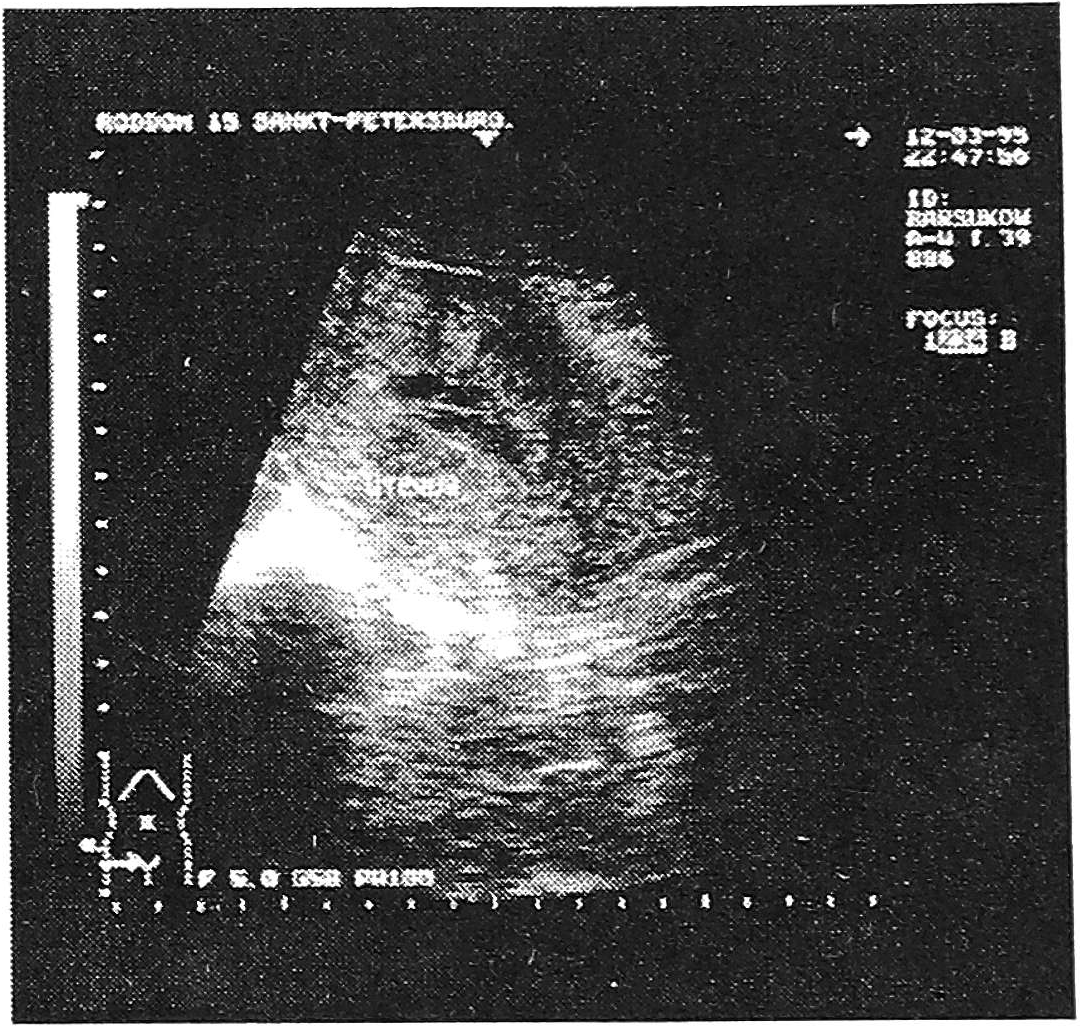

В другом случае мы наблюдали редкое осложнение после кесарева сечения - гематометру. Первобеременная первородящая 37 лет родоразрешена в плановом порядке по совокупности показаний. При этом отмечена достаточная проходимость внутренего зева и цервикального канала, что позволило вести данный случай консервативно. На эхограмме на 3-и сутки определялось неравномерное расширение полости матки, шейка не сформирована. В полости визуализируется значительное количество сгустков крови, не дающих акустическую тень (рис. 4). В динамике на 10-й день (рис. 5), сгустки определились в шейке и на выходе из нее. Полное опорожнение гематометры произошло к 16-му дню послеродового периода.

Рис. 4. Гематометра в послеоперационном периоде.

Рис. 5. Гематометра в послеоперационном периоде. Содержимое полости матки сместилось в шейку.